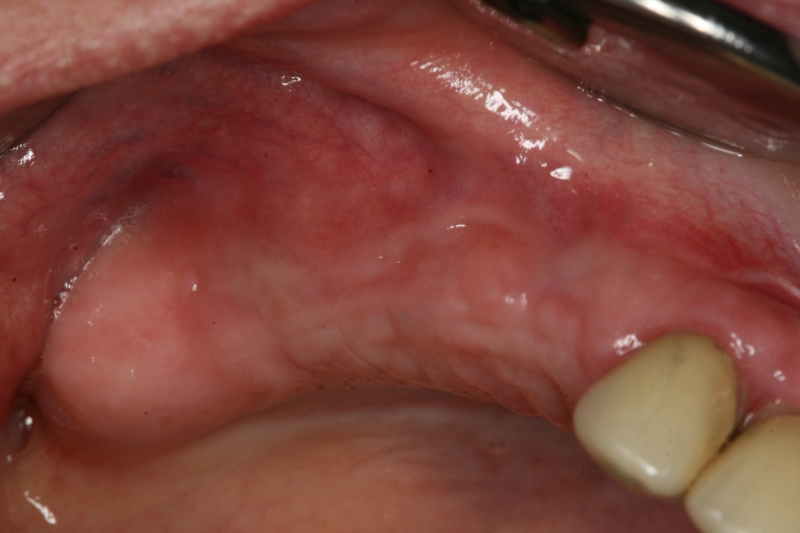

Initial clinical situation with gum recession and labial bone loss eight weeks following tooth extraction